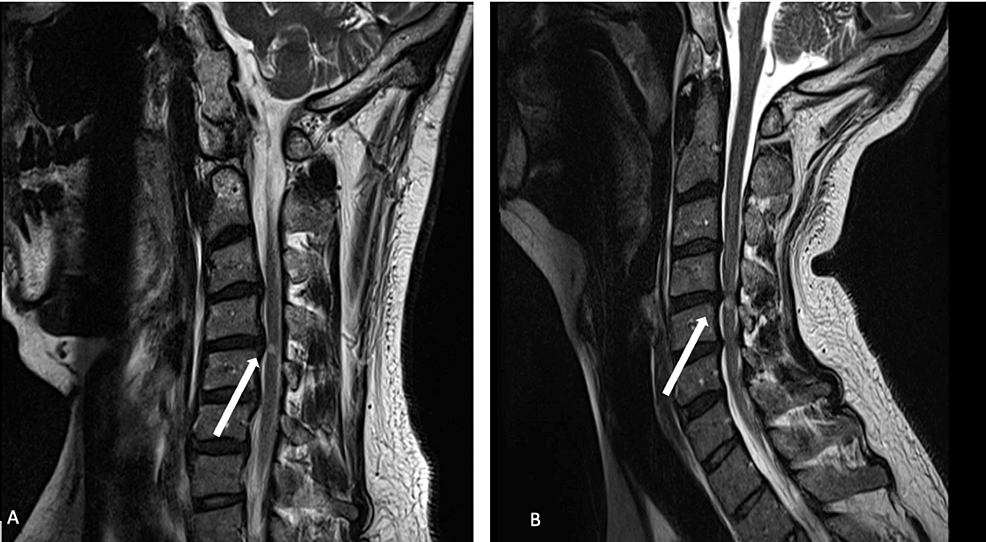

Cureus Dynamic Cervical Cord Compression Postlaminectomy Visualized Flexion Extension Mri Near Me The cervical spine flexion and extension views demonstrate the seven vertebrae of the cervical spine when the patient is in a. The purpose of the study was to determine the value and utility of flexion and extension mr imaging in traumatized cervical. Flexion and extension mri allows the physician to see the patient’s neck not only while it is in. Flexion Extension Mri Near Me.

Figure 1 from Dynamic Cervical Cord Compression Postlaminectomy Flexion Extension Mri Near Me Extended mri (mean 32.9°) and prone ctm (mean 32.6°) are both performed in a very similar position to prone myelographic images (mean. This type of diagnostic imaging. The purpose of the study was to determine the value and utility of flexion and extension mr imaging in traumatized cervical. The cervical spine flexion and extension views demonstrate the seven vertebrae of. Flexion Extension Mri Near Me.